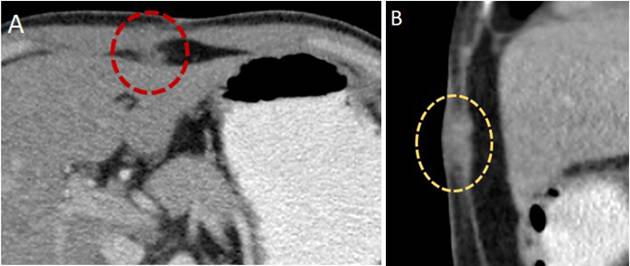

La ecografía abdominal debe hacer sospechar un CVB cuando hay engrosamiento focal e irregular de la pared de la vesícula o cuando el espesor es mayor de 10 mm. La TC y la RNM son más útiles para evaluar la extensión de la enfermedad o cuando hay masas vesiculares de buen tamaño 49 (Figuras 2 y 3). Cuando el diagnóstico se sospecha de forma intraoperatoria, el cirujano se enfrenta a una situación compleja en la que tenía programada solo una colecistectomía, y que debe ser analizada caso a caso, debido a las implicaciones de una cirugía mayor en un paciente no informado de la misma y con riesgo de morbilidad y mortalidad. Si la patología confirma el diagnóstico, se realizará la estadificación y toma de decisiones según la misma 50.

Cuando el compromiso neoplásico afecta la lámina propia, respetando la capa muscular, corresponde a un estadio T1a y no requiere intervenciones adicionales a la simple colecistectomía. Ante la presencia de estadios T1b o más, se deben realizar estudios imagenológicos de estadificación clínica, que deben incluir imágenes de alta resolución de tórax, abdomen y pelvis, en busca de linfadenopatías regionales o metástasis a distancia (Figuras 2, 3 y 4), además se debe considerar la realización de una laparoscopia (Figura 5) 30. La estadificación del CVB se muestra en la Tabla 253.